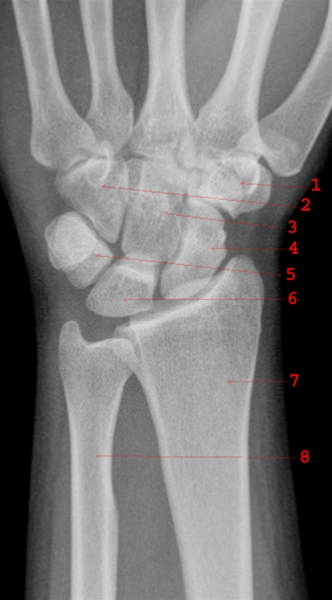

Håndled og håndrod front

Normalt håndled og håndrod.

1. Os trapezium

2. Os hamatum

3. Os capitatum

4. Os scaphoideum

5. Os triquetrum

6. Os lunatum

7. Radius

8. Ulna